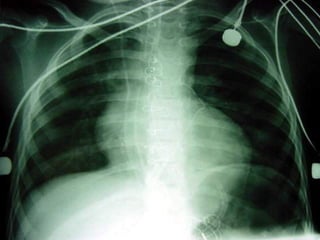

- Pneumotórax;- Pneumotórax;

- Pneumotórax- Pneumotórax